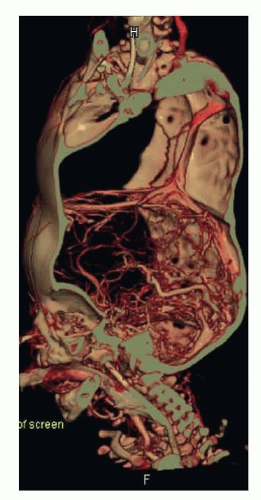

The cerebral venous drainage is shared and complex. The superior sagittal sinus is absent from both twins and is replaced by a complete or incomplete circumferential venous sinus (CVS). Mixing of the venous circulations occurs and blood generally drains preferentially to one twin (FIG 2).5